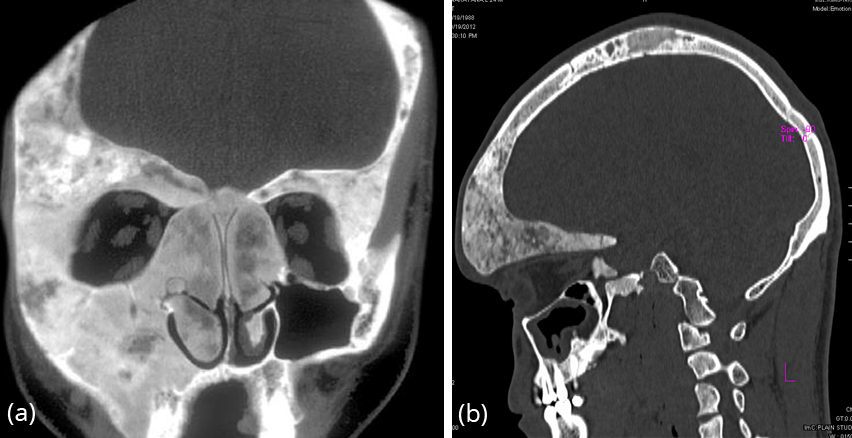

CT findings (Figure 23a,b, 24)

- Ground-glass opacities : 56 % 4

- Homogeneously sclerotic : 23 %

- Cystic : 21 %

- Well-defined borders

- Expansion of bone, with intact cortex

- Endosteal scalloping may be seen [6]

Figure 23: CT FD – (a) skull and paranasal sinuses, (b) lateral view with involvement of the vault and frontoparietal bones.